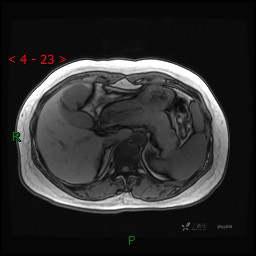

延迟肝胆期